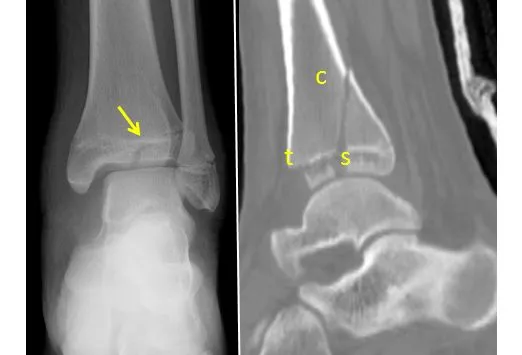

The Salter Harris IV fracture line begins at the joint surface of the epiphysis, extends directly through it, and continues through all layers of the physis and into the metaphysis. There can be significant rotation and displacement of the fracture. The two major issues in the treatment are prevention of premature closure and preservation of the joint surfaces. Accurate anatomic reduction is necessary to meet both goals; otherwise these fractures lead to growth arrest. Open anatomic reduction is preferred for these injuries if displacement occurs.

Preop and Postop Percutaneous Fixation